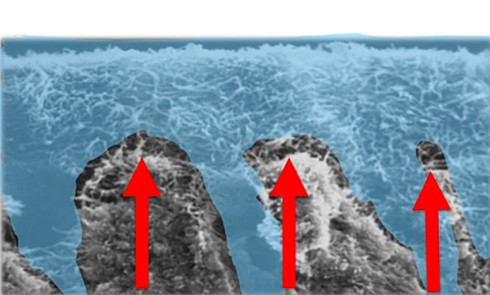

L’amélogenèse imparfaite est le nom donné à un groupe hétérogène de pathologies caractérisées par un défaut inné du développement de l’émail affectant toutes les dents des deux dentures. Ce sont des maladies génétiques dont l’origine est la mutation d’un gène impliqué dans l’amélogenèse. À ce jour, plus de 200 mutations différentes ont été identifiées, ce qui explique des phénotypes très variés [1]. Selon le stade de la maladie, l’émail est hypoplasique (défaut quantitatif), hypominéralisé, ou hypomature (défauts qualitatifs) : il est fin, fragile, tâché ou dyschromique. L’intensité des défauts peut être légère (forme frustre) ou très sévère, allant jusqu’à une absence totale d’émail. Son aspect est altéré par des dyschromies, fractures ou irrégularités de surface (fig. 1-4).